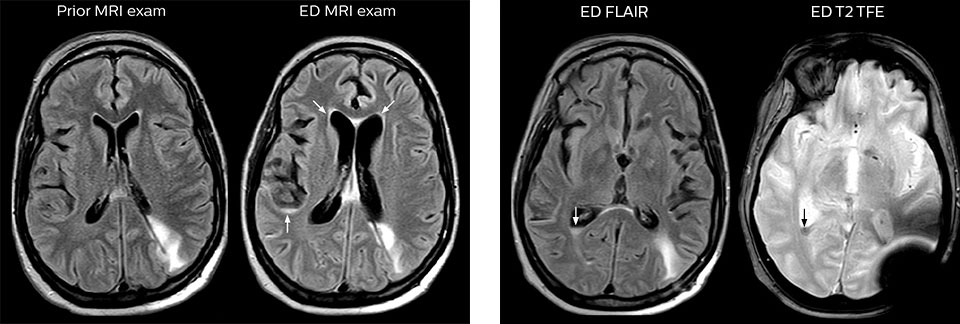

When neurological emergencies require diagnostic imaging, common practice in the ED has been to perform CT rather than MRI, even when MRI could potentially produce more informative diagnostic images of spinal cord damage, disc protrusions, soft tissue injuries, and stroke pre-cursors. [1,2] The main reason is that timing is essential in emergency cases, and CT is generally faster than MRI. The St. Joseph’s Hospital and Medical Center is now challenging this paradigm by offering rapid MRI scans within its Neurologic ED and seeing that it helps them make a richer diagnosis.

efficient as CT for referring physicians, then physicians would probably prefer MRI over CT in part of the cases. Reducing the number of CT scans for patients less than 40 years of age without significant acute findings, such as acute stroke, was also a main reason for introducing MRI into the ED. “MRI is a better test for identifying soft tissue abnormalities in the brain. What really influenced the decision on the administrative side, was the total radiation dose received by ED patients, and how this could be reduced by introducing MRI in the ED”.

“One of the most important decisions an ED physician has to make is to admit or discharge their patient. So a physician who is better informed by an MRI exam can make this decision with more confidence. By converting to a test that has a far better potential to identify issues, physicians get a better and more certain diagnosis."

"In my experience a negative MRI, because it is so sensitive to abnormality, far exceeds the value of a negative CT. A negative MRI can allow physicians to be more confident about making discharge decisions, potentially reducing the number of admissions in cases of doubt, and offering cost savings for the institute."

For Dr. Karis, the next goals for the neuro ED include converting the exams for acute stroke and TIA patients from CT to MRI, offering an alternative management option for these patients. Also, collaboration between other departments is currently underway, encouraging the performance of targeted exams with the ED MRI. These improvements in workflow and faster turnaround times may result in further reductions in scanning time.